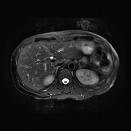

MR of a liver. American Radiology Services.